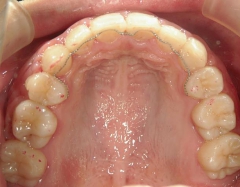

矯正歯科 治療後

矯正_灰色.pngno.18_2196_治療後_上.jpg矯正_灰色.png